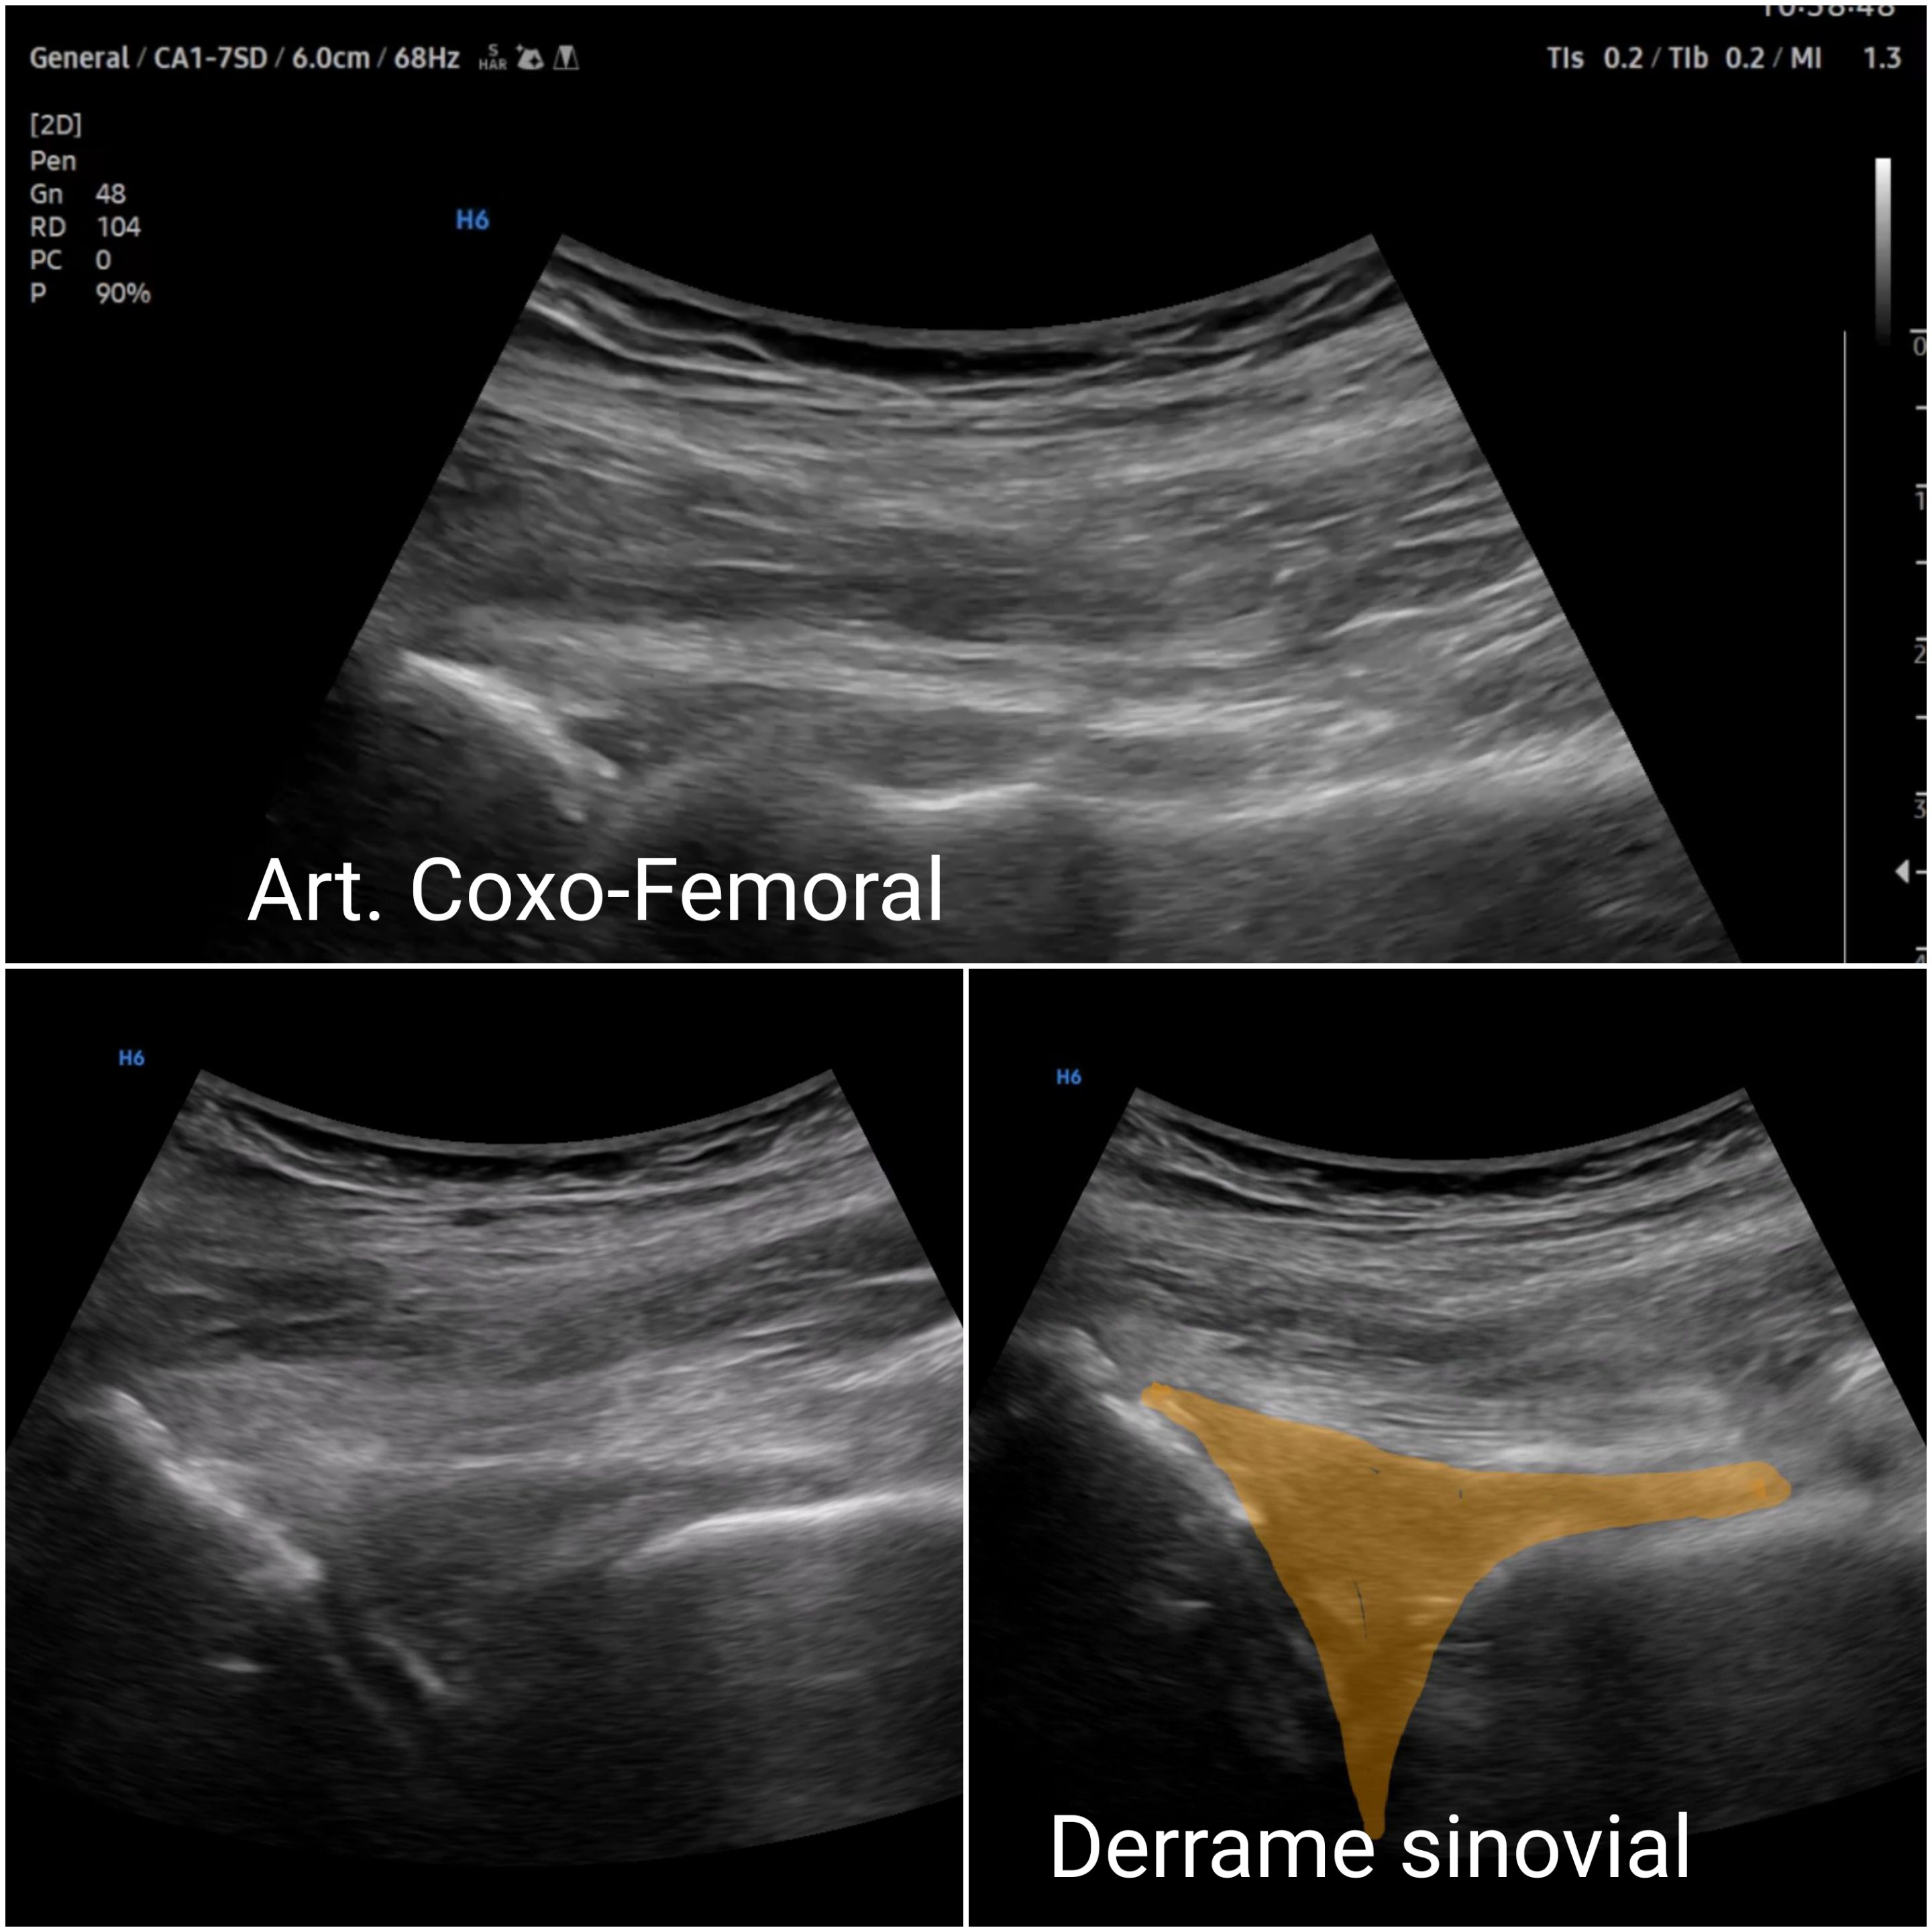

Dolor inguinal.

Presentación de 8 casos clínicos que consultan por dolor inguinal. Si bién cada caso tiene matices clínicos y de exploración, desde el punto de vista docente compatir lo que aportan los diferentes hallazgos ecográficos al siempre desafiante dolor inguinal.

Hallazgos ecográficos

La ecografía clínica, aplicada de forma sistemática con maniobras dinámicas, complementa el abordaje del dolor inguinal reduciendo la incertidumbre, la demora diagnóstica y permite orientar mejor dicha patología así como descartar patología escrotal o trombosis venosa.